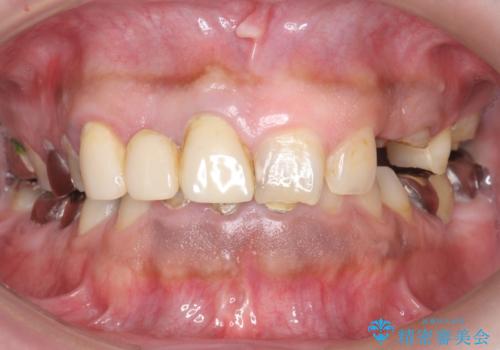

オールセラミッククラウン ブリッジによる欠損歯の補綴

- 歯がない左側でものが咬めず、右側で咬むと歯が痛むので診て欲しいといらっしゃった方の症例です。

根尖病変が認められる歯は再根管治療を行い、歯根が破折していた左上4は抜歯しました。

インプラントは希望されなかったため、左側は1番から7番のロングスパンブリッジによる補綴を行いました。